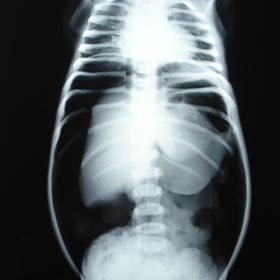

Hirschsprung's Disease

Traditionally, three stage surgery was done but in our set up; we have started single stage surgery (Laproscopic or Endorectal) without the need for colostomy. Till now, more than 100 patients were benefited.